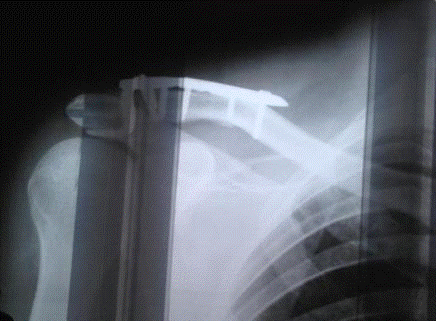

8. Rg - графия правой бедренной кости от 28.08.13

Заключение: На Rg - графии правого плечевого сустава отмечается вывих акромиального конца правой ключицы с явлениями формирования мазоли.

2.      R-графия правой ключицы: вывих акромиального конца правой ключицы.

Rg - графия правой бедренной кости от 28.08.13